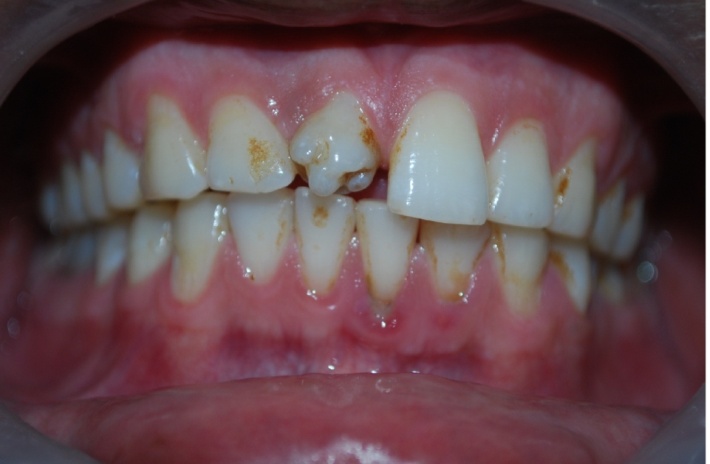

A 32-year-old male patient reported to the Department of Oral Medicine and Radiology for routine check-up. This was the patient’s first visit to a dentist. His medical and family histories were non-contributory. There were no findings indicative of any syndrome. An intraoral examination of maxillary right central incisor revealed a morphologically altered crown with multiple small cusps and a prominent central cusp (Figures 1 and 2). There were 5 small cusps and a prominent central cusp. Presence of talon cusp in relation to teeth #12, #13 and #33 was also seen. Mild stains were present on the occlusal surface of central incisor with pit caries. Intraoral periapical radiograph revealed prominent talon cusp at the center surrounded by small cusps along with three impacted supernumerary teeth at the periapex. The root, lamina dura and periodontal ligament space of tooth #11 appeared to be normal (Figure 3). Examination of the remaining dentition showed no obvious abnormalities. The patient was told about the condition. Routine scaling and oral prophylaxis were performed. Prosthetic crown in relation to tooth #11 was planned to correct the esthetic appearance and surgical removal of impacted teeth was suggested. Since the patient was asymptomatic, he refused to undergo extraction of the impacted teeth. However, he was advised to undergo prophylactic enameloplasty of the talon cusps, followed by topical application of a desensitizing agent. He was also informed about the possible consequences of the impacted teeth and a regular clinical and radiographic follow-up of the impacted tooth was suggested.

Figure 1.Photograph showing labial and incisor aspect of central incisor.

Figure 3. Intraoral photograph showing an unusual and morphologically altered central incisor with 5 small cusps and large central cusp.